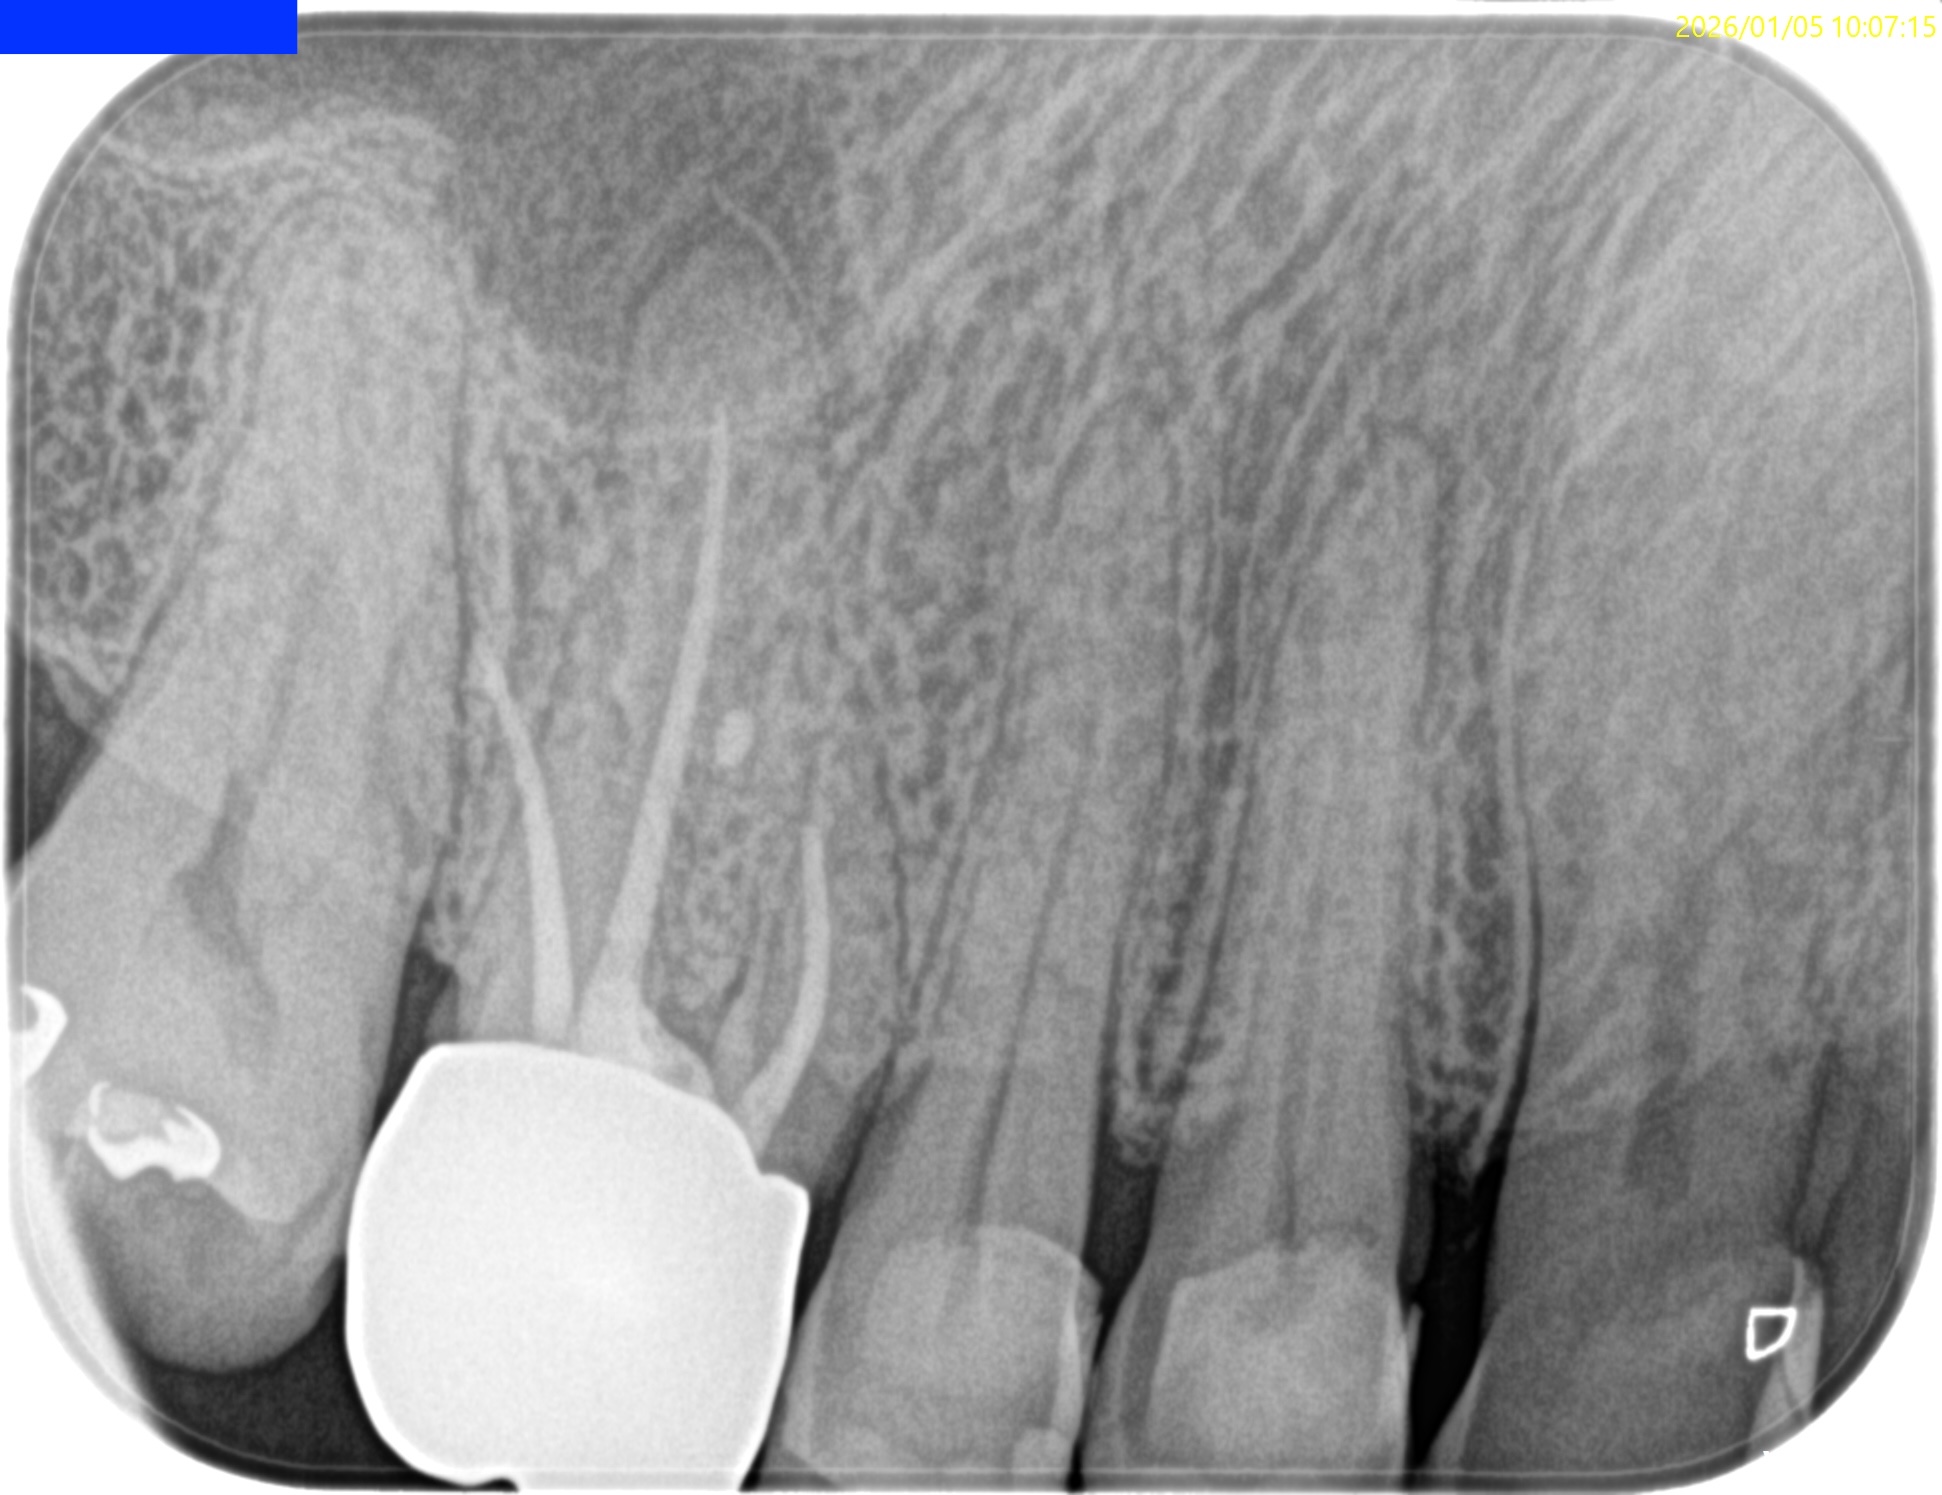

Pre-op Endo test(2025.1.27)

MB,DBのApexが歯槽骨から透けて見えている。

圧痛の原因はこれだ。

そしてSinus tract。

Pulp Dx: Pulp Necrosis

Periapical Dx: Chronic apical abscess

Recommended Tx: RCT